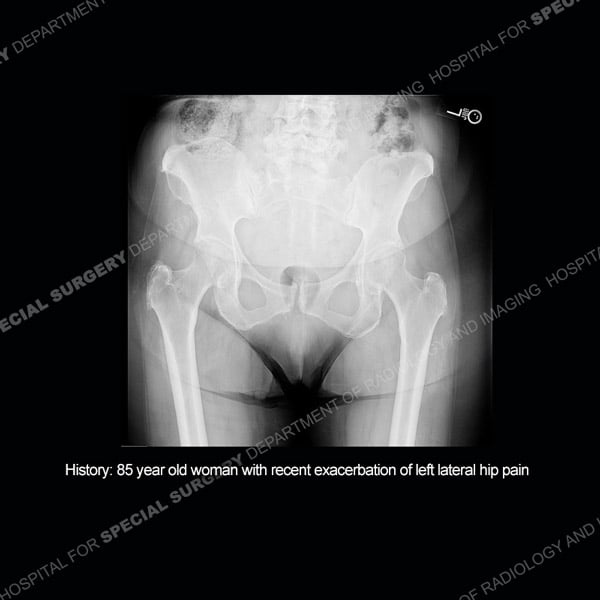

Featured Case of the MonthCase 215: 85-year-old woman with recent exacerbation of left lateral hip pain.